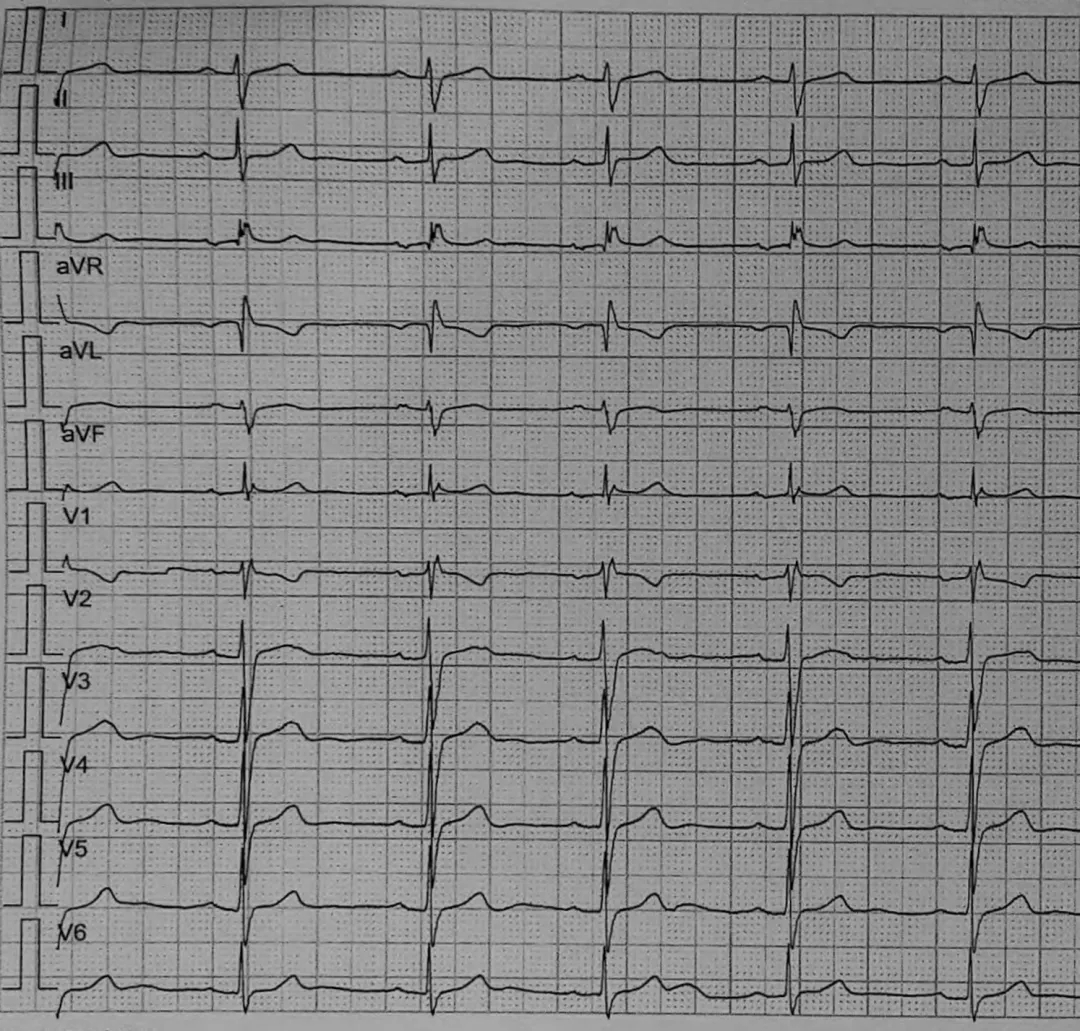

患者33岁男性,因发现心脏杂音2个月入院(2021年5月21日)。当时体格检查于第三肋间闻及2/6级舒张期杂音;ECG显示窦性心律,PR间期174 ms,QRS波时限100 ms,额面QRS电轴正常(图1A);动态心电图监测结果显示,在运动诱发的窦性心动过速期间,出现间歇性不完全性右束支传导阻滞(RBBB)伴电轴右偏(图1B);超声心动图显示BAV脱垂伴重度主动脉瓣反流,左心室轻度扩大(舒张期前后径:58 mm),左心室射血分数为65%。患者既往体健,无相关疾病史。

患者住院期间的心电图

注:(A)入院时。(B)术前运动性窦性心动过速时出现不完全性右束支传导阻滞。(C)手术后立即显示不完全的右束支传导阻滞。

术后ECG示窦性心律伴不完全性RBBB,电轴正常。超声显示主动脉瓣形态正常,微量反流。术后第3天因心律平稳拔除心外膜起搏导线。然而,在术后第6天(2021年6月1日),患者诉突发心悸,ECG显示心律不齐和间歇性宽QRS波群(图2),几分钟后恢复正常。约4小时后发生晕厥,远程监护显示AVB,间歇性交替通过左或右束支传导,进而演变为全心停搏,最长停顿达7.4秒(图3C)。

图2 术后第6天患者出现心悸时的心电图